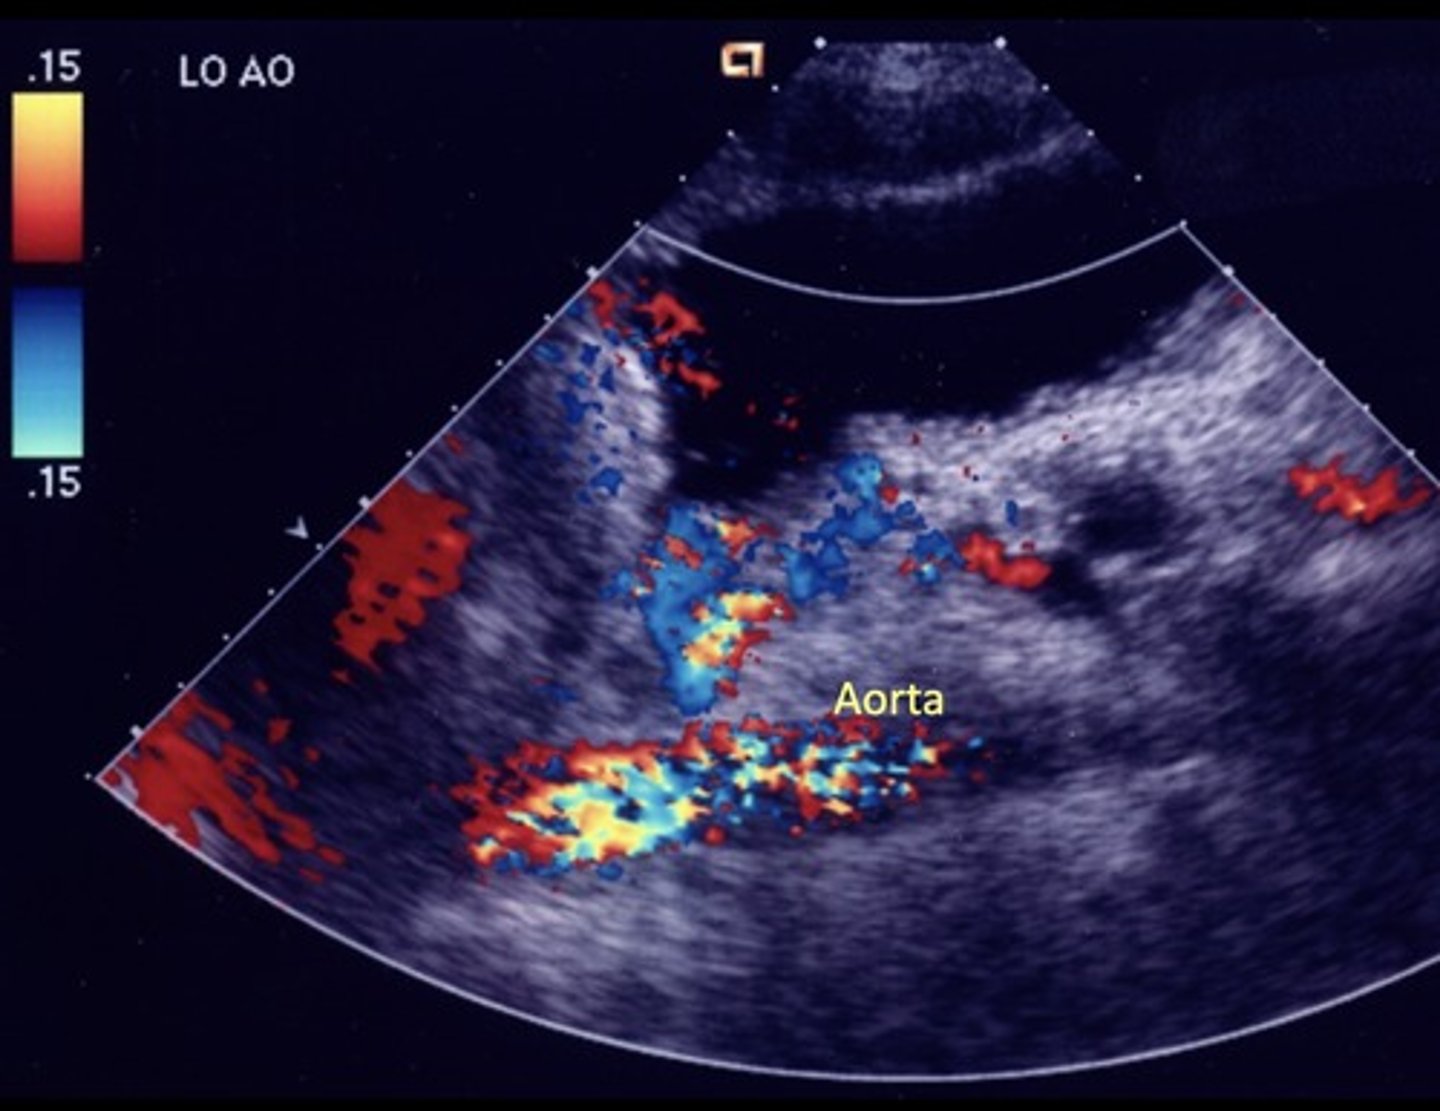

Celiac Artery Occlusion

Results in SMA collaterals diverting blood through gastroduodenal artery toward the liver and spleen

Hepatic Artery Retrograde Flow

Due to celiac artery occlusion

Blood flows towards splenic artery - RABT color pattern

Common Trunk Variant

Celiac and SMA come off common trunk

Prominent IMA

Due to SMA occlusion